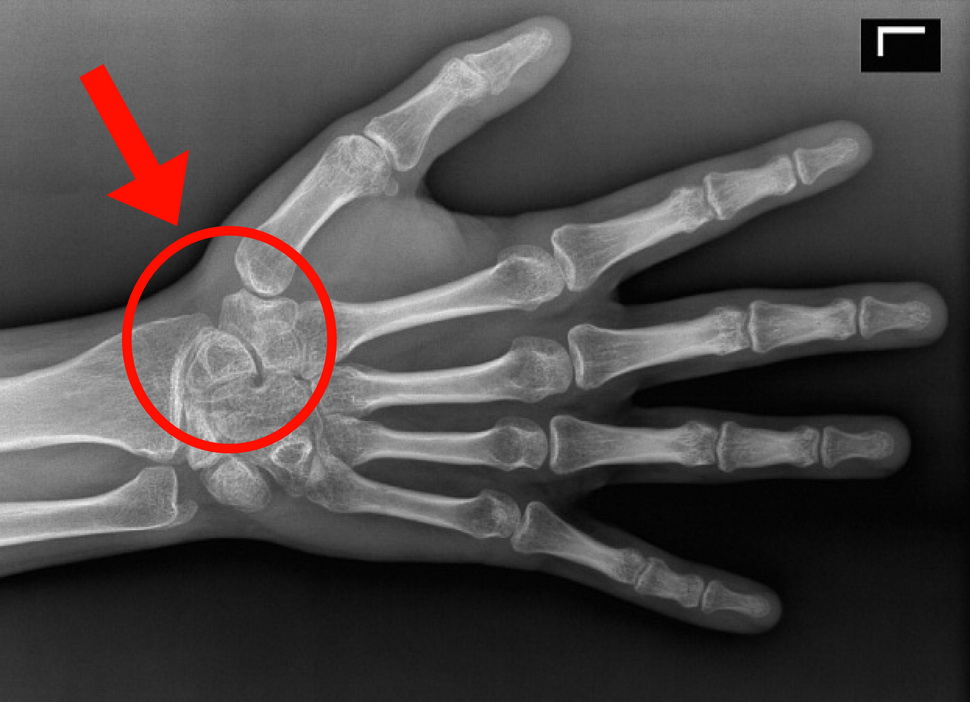

Рентген: Как выглядит здоровая пястная кость

Раздел: Картинки на заметку